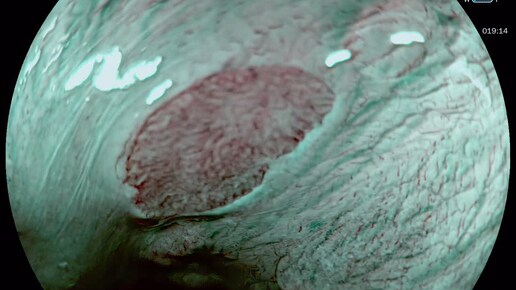

Желудочный эпителий в пищеводе: причины, симптомы, лечение